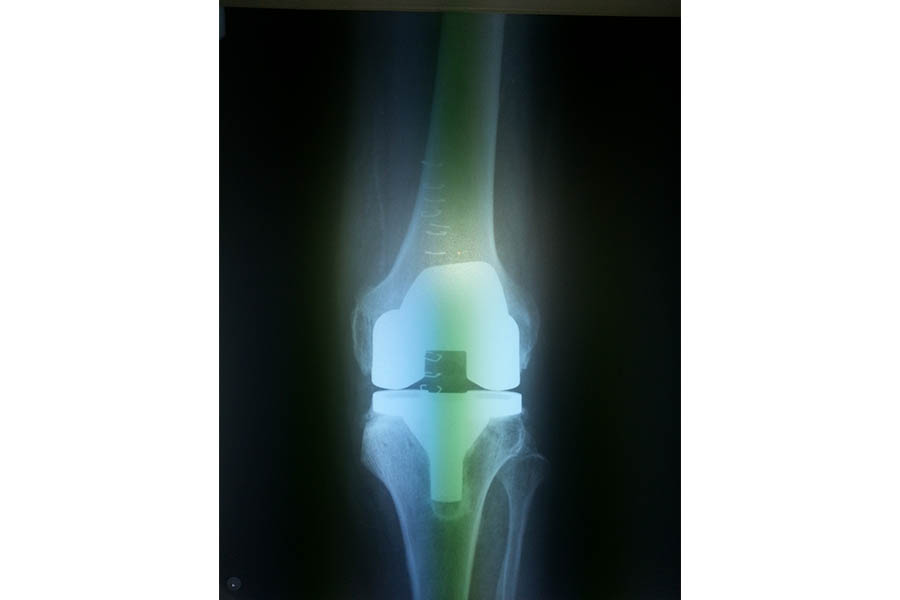

Total Knee Replacement

Case 2